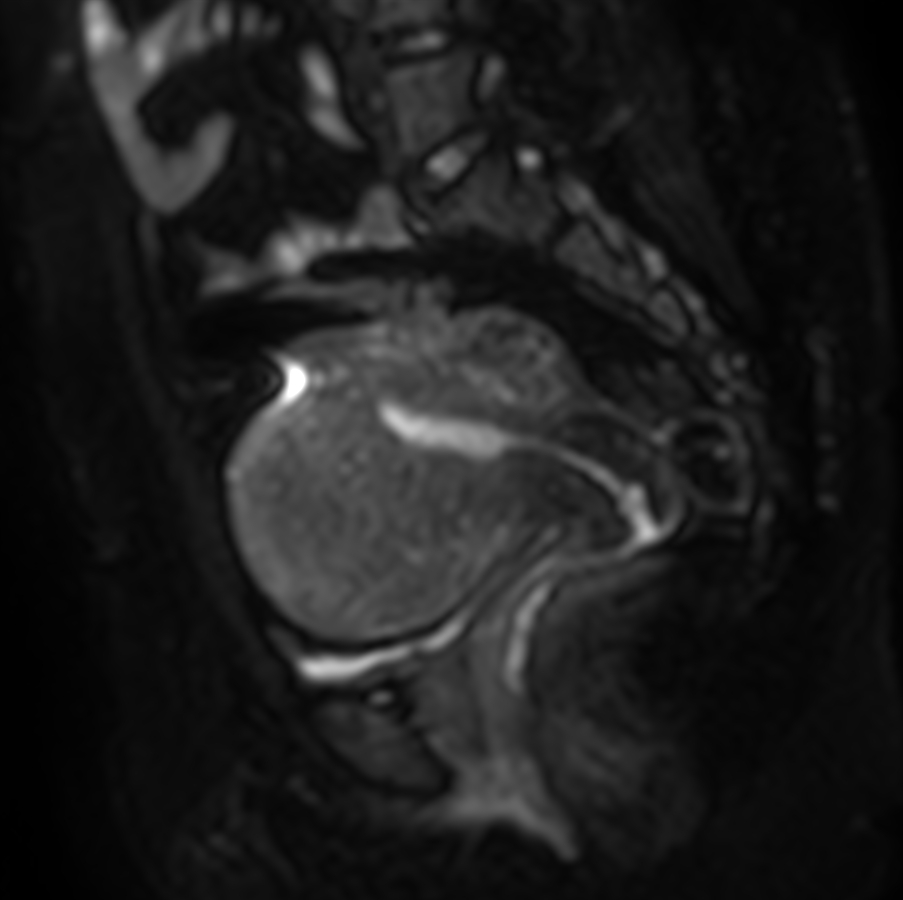

Sagittal DWI (b1000)